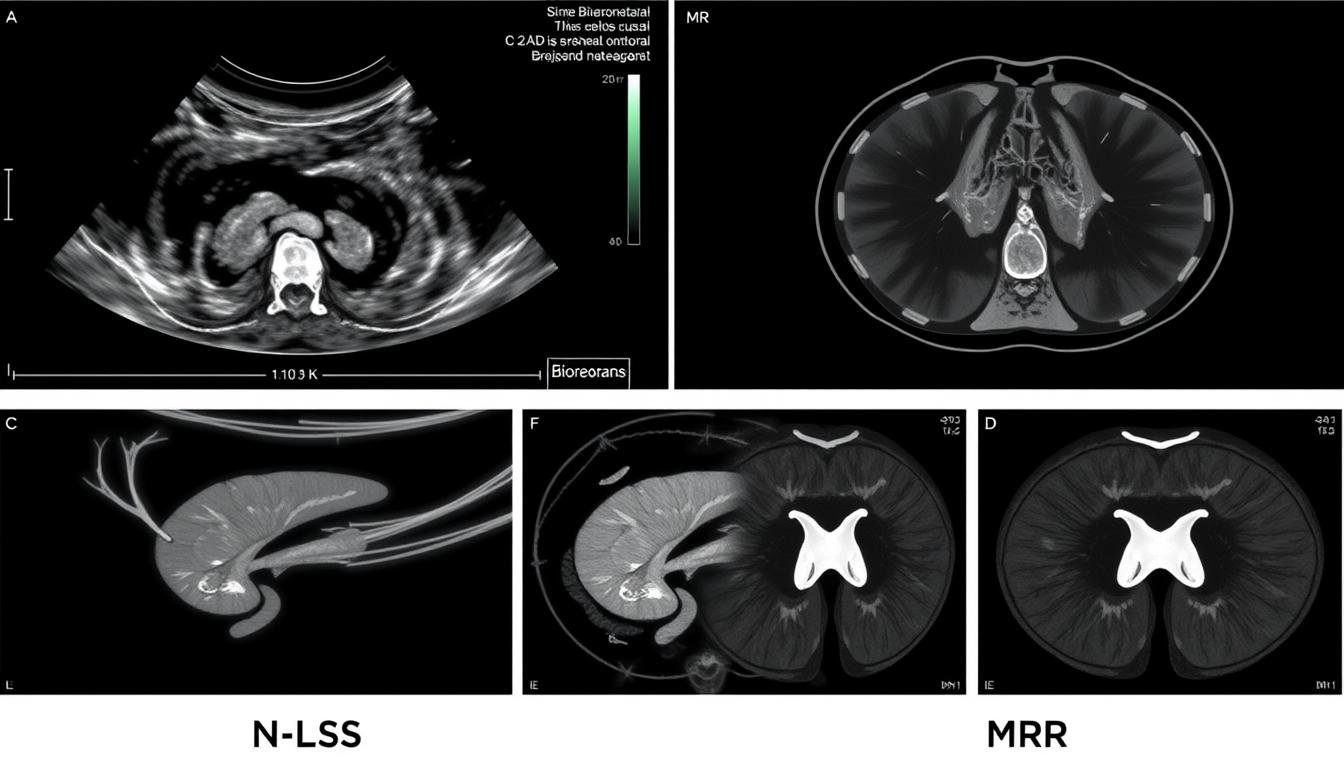

Porównanie wyników Biorezonans NLS z tradycyjnymi metodami diagnostycznymi